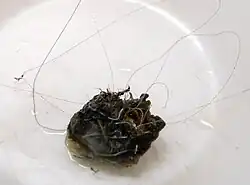

Post-embolization arteriogram showing coiled aneurysm (indicated by yellow arrows) of the posteriorcerebral artery with a residual aneurysmal sac. | |